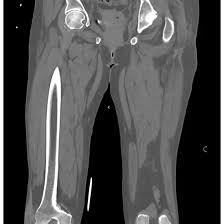

NCCT Right Thigh

Are you looking for an affordable NCCT Right Thigh scan? At Medifyhome, we offer competitively priced MRI and CT scans, partnering with top NABL-certified diagnostic centres and clinics. Our facilities ensure high-quality imaging and accurate results. An NCCT (non-contrast computed tomography) scan of the right thigh is a diagnostic imaging procedure that produces detailed cross-sectional images of the thigh’s bones and soft tissues without the use of contrast agents. This scan is commonly performed to evaluate fractures, tumours, infections, and soft tissue abnormalities in the thigh region. During the procedure, the patient lies still on a table while the CT machine captures multiple images from various angles. The resulting high-resolution images help healthcare providers accurately assess any issues affecting the thigh. The NCCT scan is quick, safe, and particularly useful for patients who may be allergic to contrast materials or require urgent evaluations. To book an appointment for an NCCT Right Thigh scan, visit our platform, Medifyhome, or contact us at +919100907036 or +919100907622 for reasonable prices.

An NCCT (non-contrast computed tomography) scan of the right thigh is a diagnostic imaging test that produces detailed cross-sectional images of the bones, muscles, and soft tissues in the right thigh without the use of contrast agents. This scan is used to evaluate various conditions, including fractures, tumours, infections, and soft tissue injuries. It provides high-resolution images that help healthcare providers accurately diagnose and assess the extent of any issues affecting the thigh. The procedure is quick and generally safe, making it suitable for patients who may have allergies to contrast materials or need immediate evaluation. Overall, the NCCT scan is a valuable tool in diagnosing and guiding treatment for thigh-related concerns.